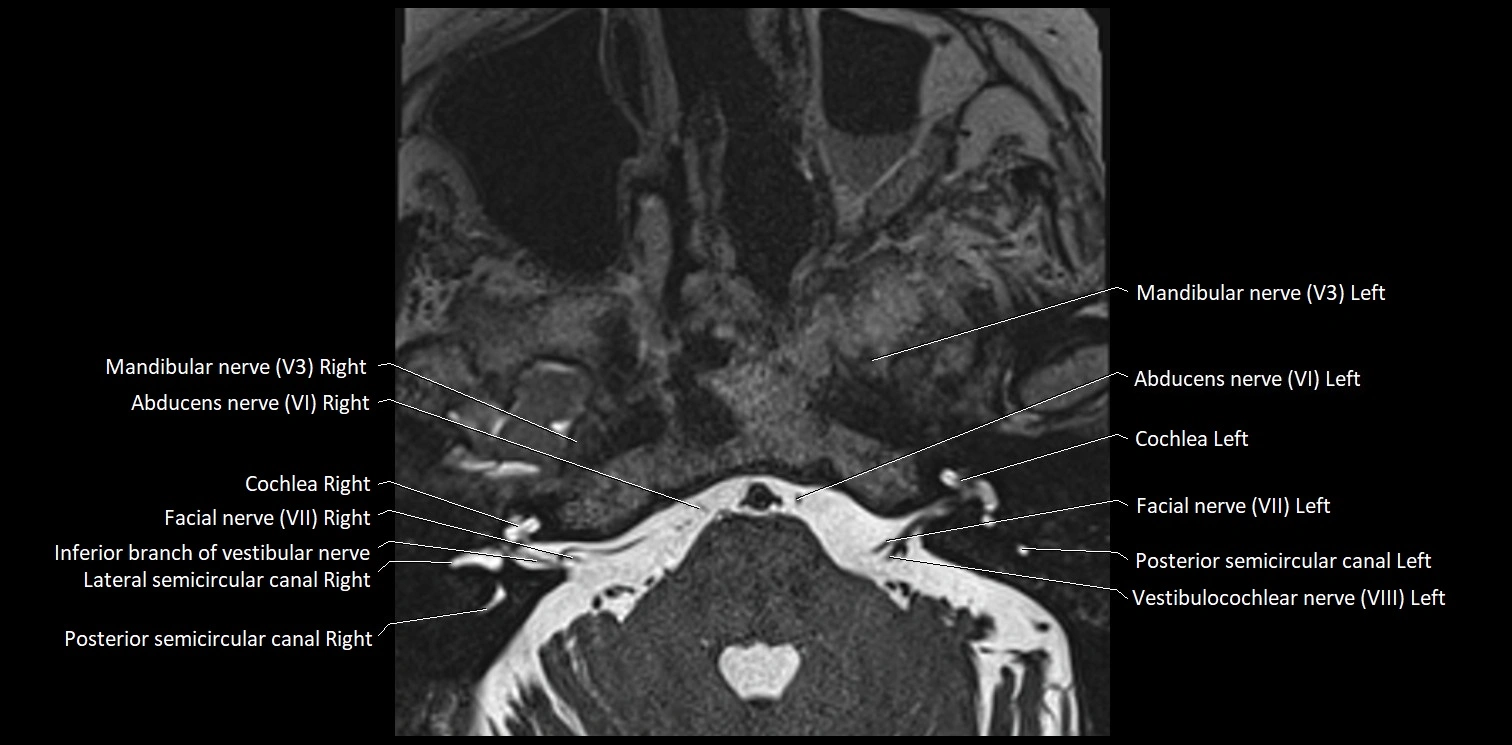

MRI Appearance

• The abducens nerve is a small, thin, linear structure

• Best visualized on high-resolution T2-weighted 3D MRI sequences (e.g., FIESTA or CISS)

• Seen as a hypointense (dark) line running from the brainstem at the pontomedullary junction, traversing the prepontine cistern, and entering Dorello’s canal under the petrosphenoidal ligament, then into the cavernous sinus, and finally the orbit

• May be challenging to visualize in standard MRI due to its small size

• Pathology may be inferred by absence, displacement, or enhancement of the nerve